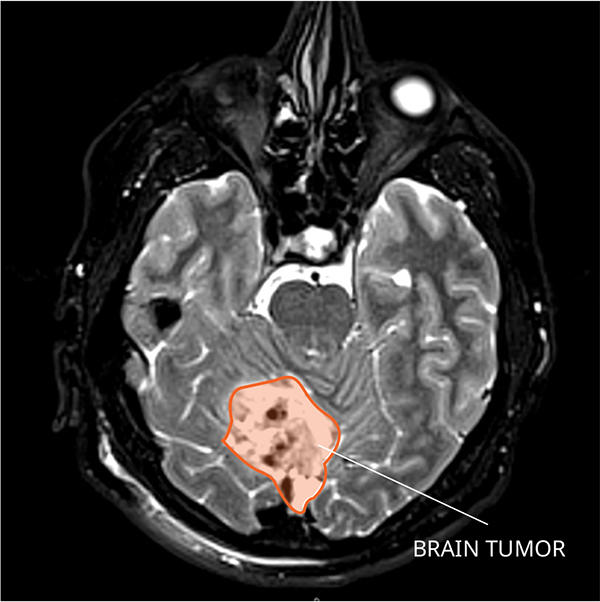

What Do Medulloblastomas Look like on an MRI?

Medulloblastomas usually appear as a solid mass in the cerebellum, which is the portion of the brain in the back of the head between the cerebrum and the brainstem. The tumor often brightens with contrast. It can also block the cerebrospinal (CSF) pathways, causing an abnormal build-up of fluid, which increases pressure on the skull. This is known as hydrocephalus. Once the mass is diagnosed as a medulloblastoma, a magnetic resonance imaging (MRI) scan of the spinal cord can show if it has spread.